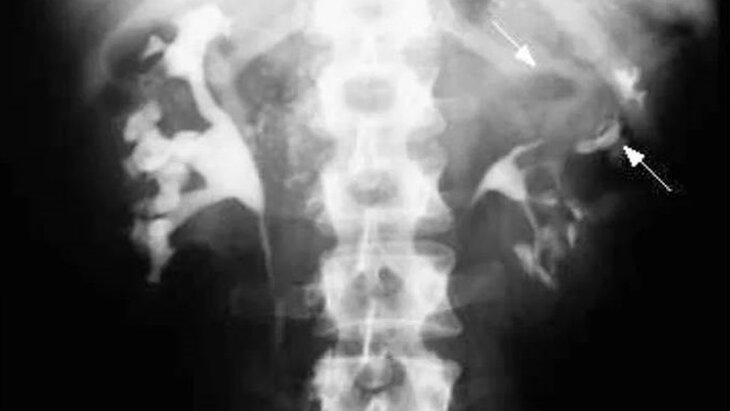

Фото: министерство здравоохранения Московской области

По итогам комплексного обследования врачи диагностировали 10-летней девочке абсцесс левой почки – патологии, характеризующейся гнойным воспалением ткани органа. При отсутствии срочного лечения повышается вероятность сепсиса, почечной недостаточности и распространения инфекции на другие органы.